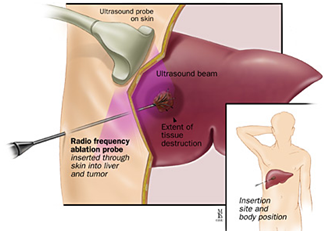

- אבלציה באמצעות גלי רדיו (RFA, Radiofrequency Ablation) (תמונה מספר 2) – מערבת נזק הנגרם על ידי חום לרקמת הגידול. שיטה זו מצריכה פחות טיפולים לעומת הזרקה מלעורית, ובמחקרים השוואתיים משיגה תוצאות טובות יותר. בחולי שחמת מדרגה A ההישרדות לחמש שנים מגיעה ל-50-65% לאחר טיפולים בשיטה זו.

- חסרונות האבלציה הם עלות ותופעות לוואי בעיקר תפליט פליאורלי (Pleural effusion) ודימום לחלל הצפק (Hemoperitoneum). יעילות שיטה זו זהה לניתוח בחולי סרטן כבד ראשוני בדרגות מוקדמות. שיטת טיפול זו מומלצת כשיטת האבלציה העיקרית בגידולים קטנים מ-5 ס"מ